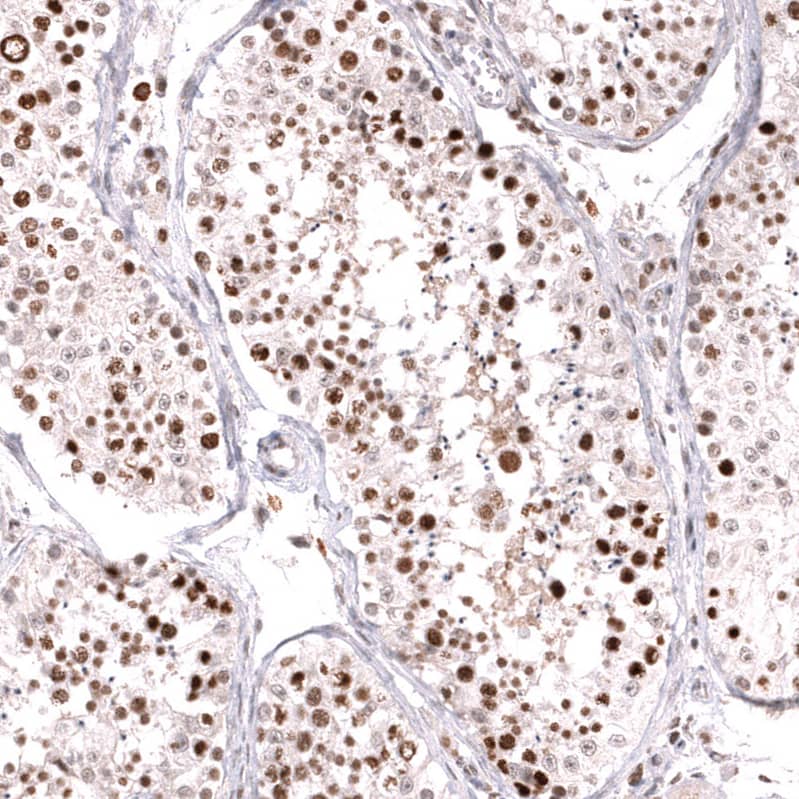

Immunohistochemistry-Paraffin: MSH6 Antibody (CL13844) [NBP3-24582]

Staining of human breast cancer (ductal carcinoma) shows strong nuclear positivity in tumor cells.